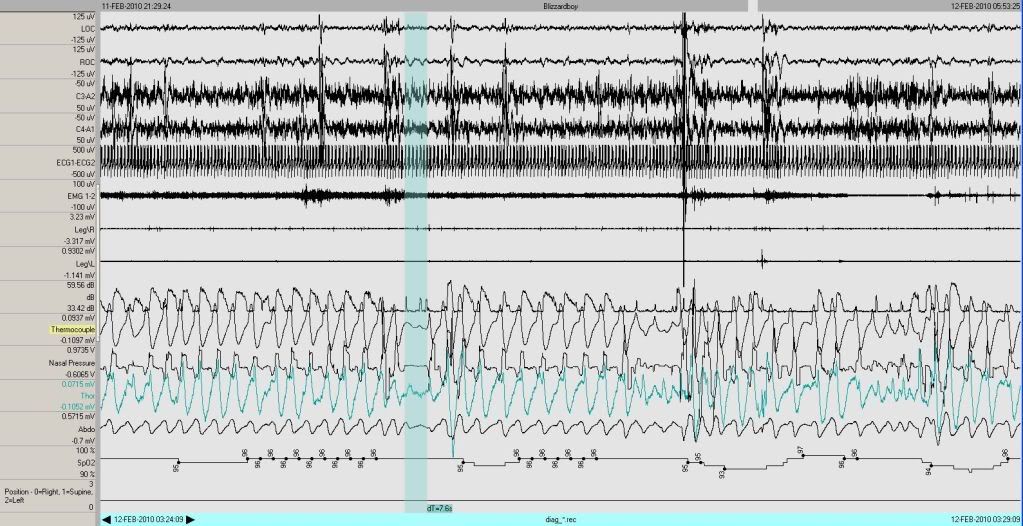

...so let's look grossly (30 minute view)(BTW, it would certainly be helpful to do this live to see the differences as we pass from 30 second to 1, 5, 10, 30 minute views and more, but the time frame is noted at the bottom of the epoch, and when in doubt, count up the respiratory rate. ~12 breaths = a minute (assuming he's breathing).

ANYWAY....

Image

If we're going to score hypopneas, we need to know the desats.